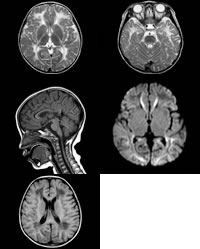

辅助检查:头颅磁共振成像(MRI)示双侧大脑半球脑白质弥漫性、对称性长T1长T2信号,信号强度与脑脊液相近,弓形纤维大部受累。内囊后肢、外囊、最外囊、脑干背侧受累(图1,2)。胼胝体内下缘受累(图3)。双侧尾状核头轻度肿胀,T2WI呈稍高信号。豆状核及丘脑未见异常。液体衰减反转恢复(FLAIR)像双侧额顶叶白质可见对称性低信号,部分区域趋于囊性变,残存少量线状稍高信号(图4)。小脑萎缩,小脑白质内见T2WI及FlAIR高信号区。磁共振弥散加权成像(DWI)半卵圆中心、顶枕叶及胼胝体可见条片状高信号(图5),余病变区呈低信号。

图1、2 T2WI轴位,示双侧大脑半球脑白质弥漫性、对称性长T2信号

图3 T1WI矢状位,示受累白质呈低信号

图4 FLAIR轴位,双侧额顶叶深部脑白质呈低信号

图5 DWI轴位,胼胝体、枕叶可见高信号, 百拇医药